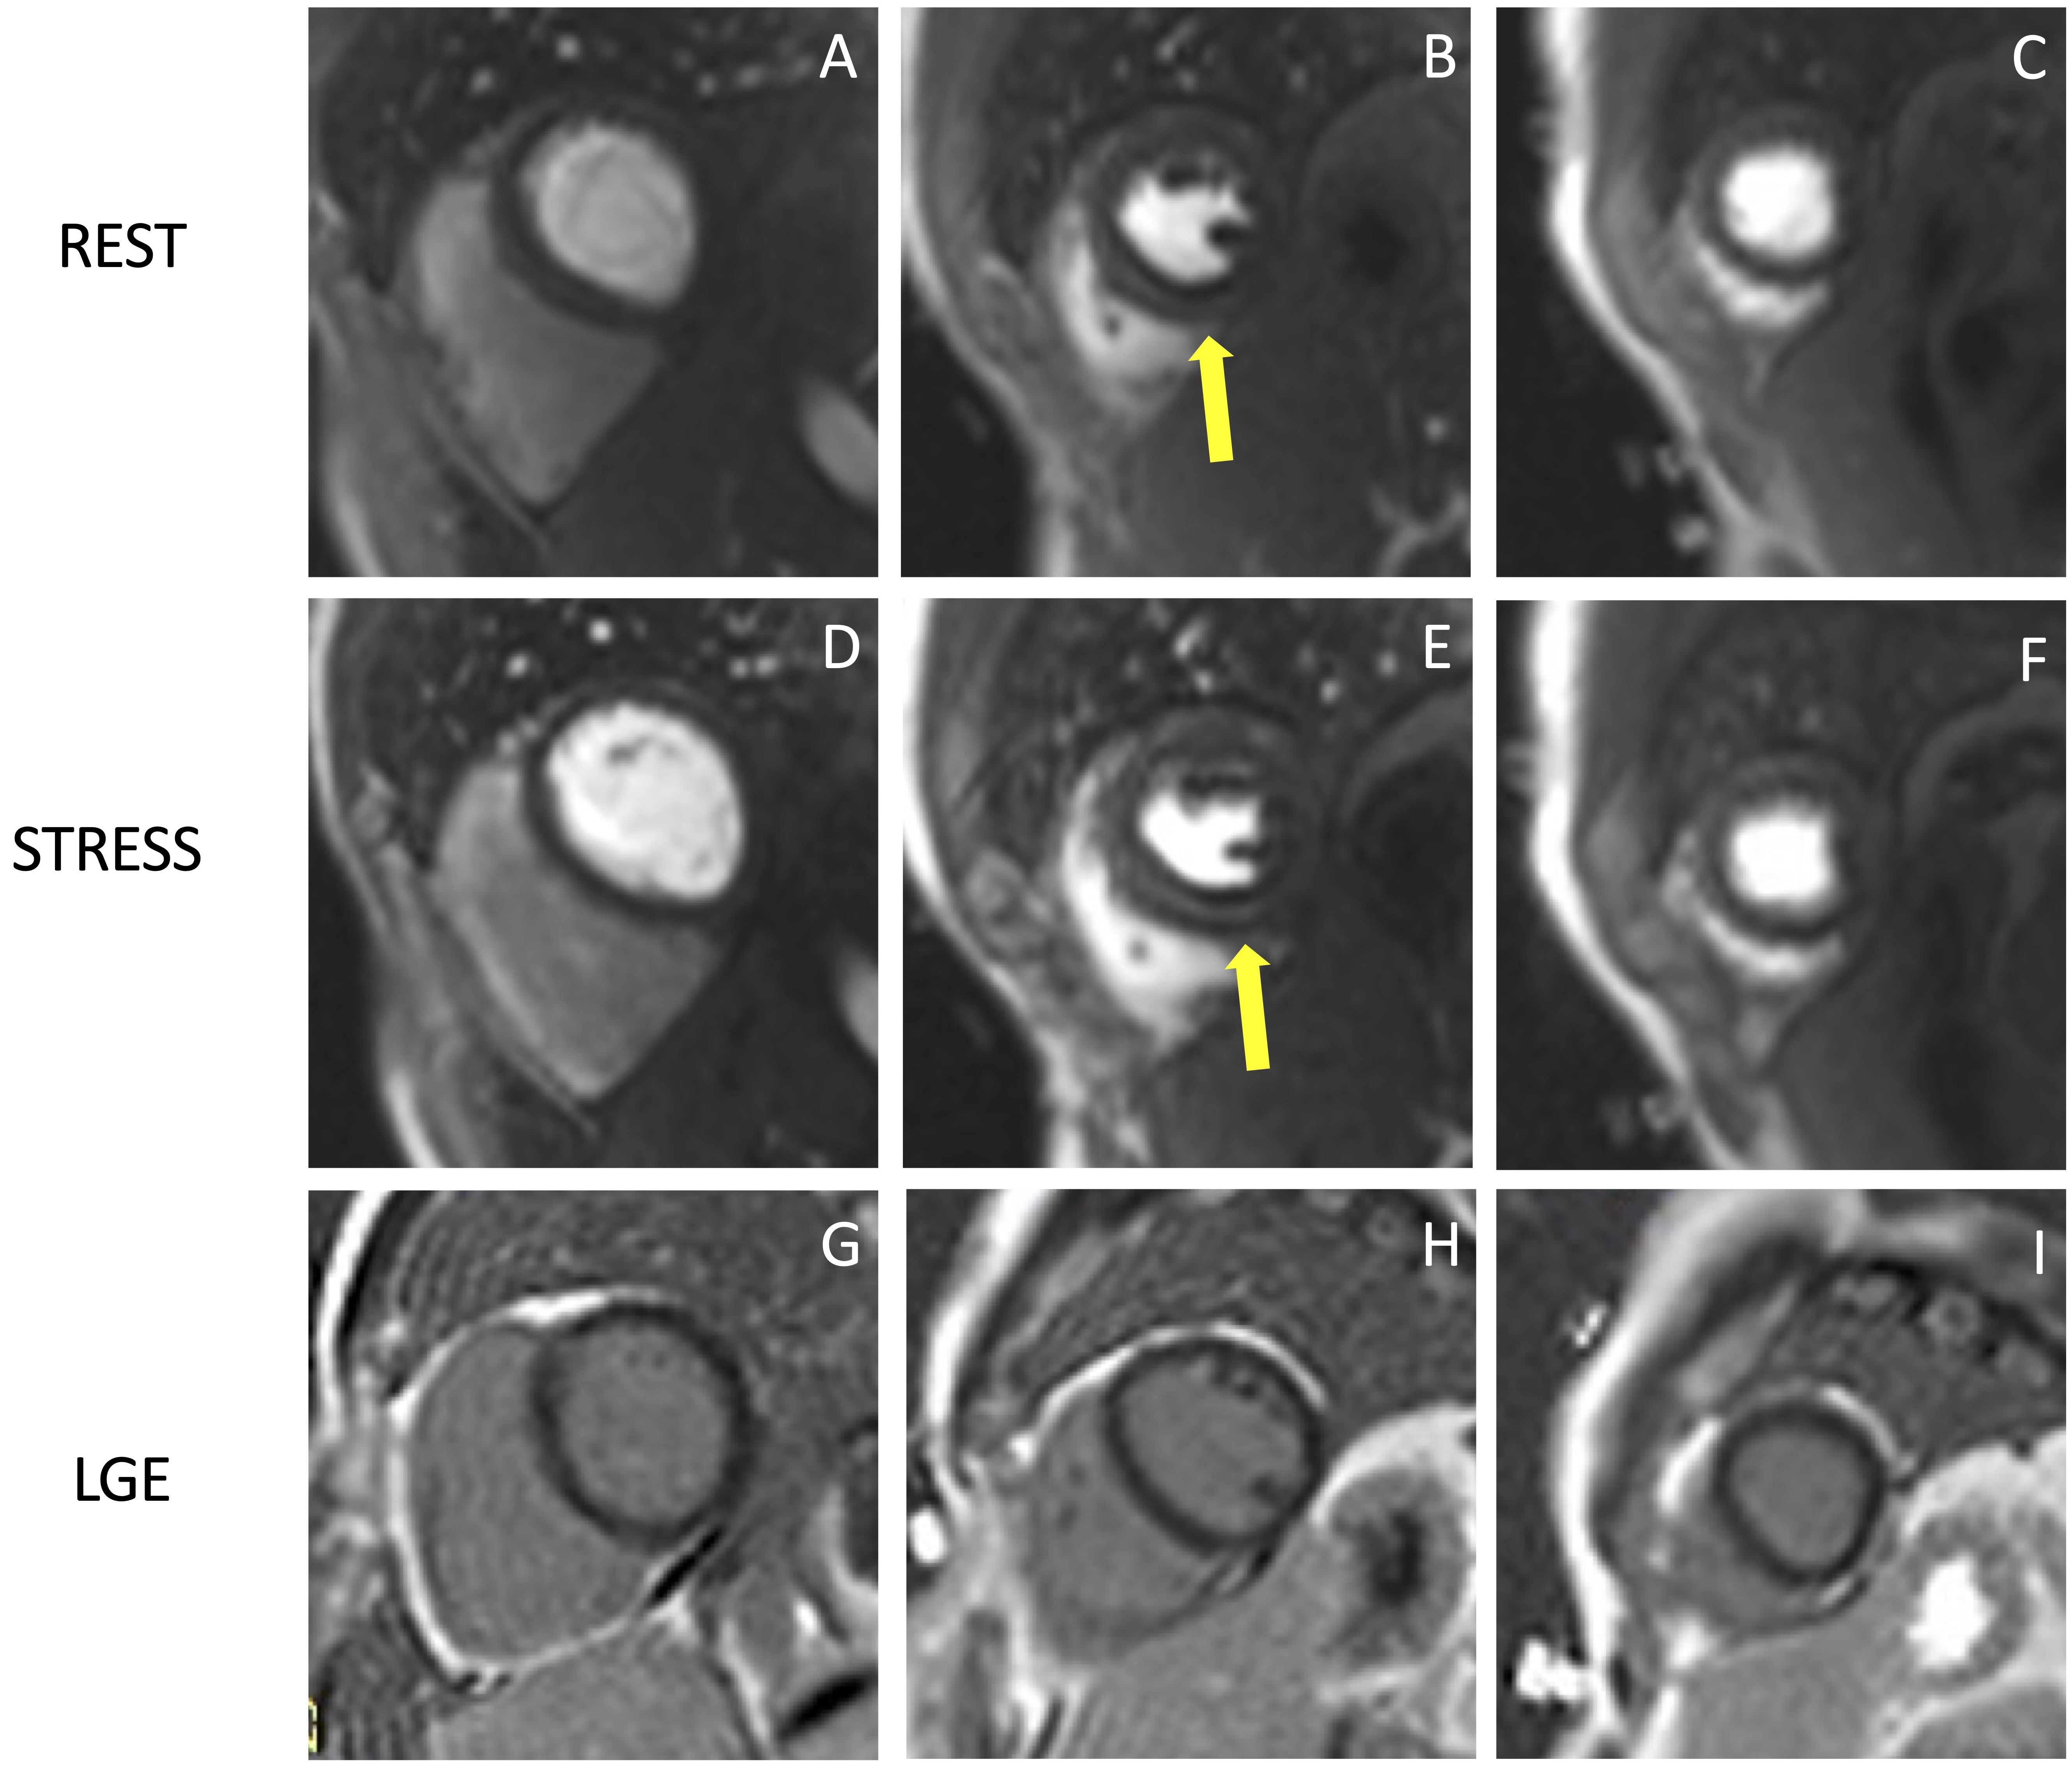

Stress CMR has been shown to be a safe and feasible technique, with good diagnostic quality. In a multicentre prospective registry of about 12,000 referral patients, stress CMR showed an excellent safety profile with higher incidence of mild complications and minor symptoms in dobutamine stress CMR compared to other vasodilators [33]. The safety of stress CMR has been demonstrated in patients with heart failure with reduced ejection fraction without any adverse event in a population of 1053 patients [34]. Stress CMR was well tolerated also in consecutive patients with MR-conditional pacemakers, with no significant change in lead thresholds or pacing parameters [35]. Pezel et al. [36] demonstrated the feasibility of vasodilator stress CMR in more than 600 patients with atrial fibrillation and suspected or stable coronary artery disease (CAD). Fig. 4 and Fig. 5 show two examples of stress CMR clinical cases. Fig. 6 shows how to implement stress CMR in clinical practice.

Fig. 4.Example of positive CMR adenosine-stress perfusion. We present the case of a 73-year-old man with new onset of ventricular arrythmia on exercise test and a history of previous ACS and RCA angioplasty. Short axis rest and stress perfusion images are shown respectively at the basal (A,D), mid-ventricular (B,E), and apical (C,F) level. The stress images show the presence of a perfusion defect, appearing as subendocardial hypointense area in the inferior septum, inferior wall and in the mid portion of the anterior and antero-septal walls (yellow arrow heads). Corresponding LGE images (G,H,I) show no myocardial scarring. The patient underwent a coronary angiography which revealed diffuse CAD with severe stenosis at the proximal tract of the LAD artery (yellow arrow line, J). and at the origin of the intermediate and the first diagonal branches (yellow arrow line, K). Moreover, there was an intrastent occlusion in the RCA with a collateral circulation (yellow arrow line, L). CMR, cardiovascular magnetic resonance; ACS, acute coronary syndrome; CAD, coronary artery disease; LAD, left anterior descending; LGE, late gadolinium enhancement; RCA, right coronary artery.